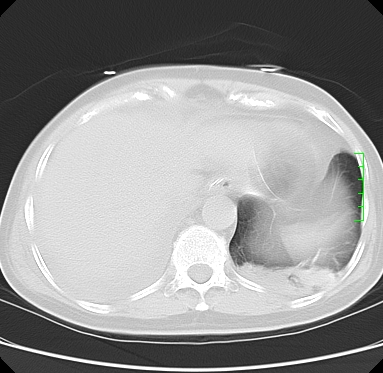

icu病人,几天都没明确诊断。m,76y,咳嗽、咳痰1周,伴气促,右胸痛入院,pe:t38.3c p135 r25 bp135/85。双肺可闻及大量湿罗音,心、腹未见明显异常。诊断:1心衰?2肺部感染?3冠心病?

11号ct

双肺感染性病变,下叶膨胀不全,胸水,左室大。

1)两肺感染性病变(右肺下叶肺脓肿可能)。2)双侧胸腔积液,以右侧为甚。

ards,肺感染性病变,右下叶实变,双侧胸腔积液,右侧为著,叶间胸膜积液,右上肺陈旧性tb纤维灶,左室大。